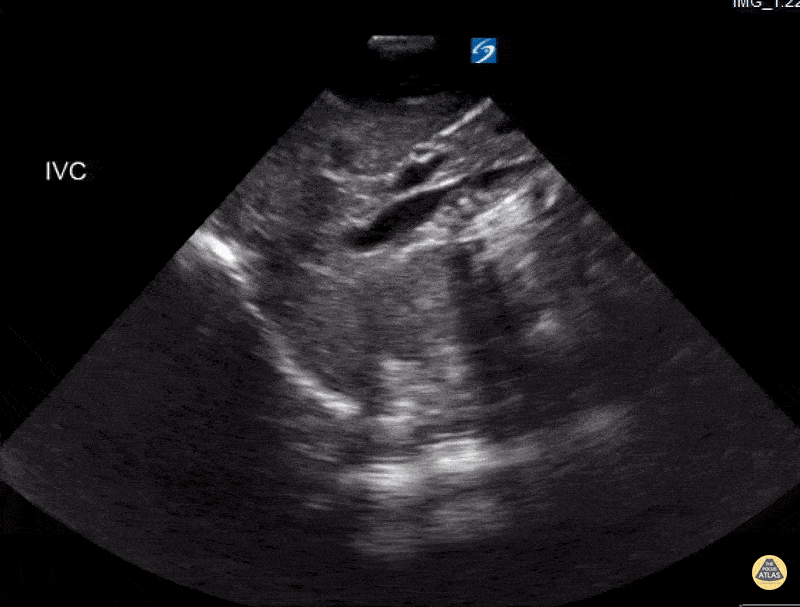

Peds-Cardiac - IVC Hypovolemia

6 year old with vomiting and diarrhea. IVC shows fluid tolerant with significant flattening with respirations. Contributor: Kathryn Pade, MD